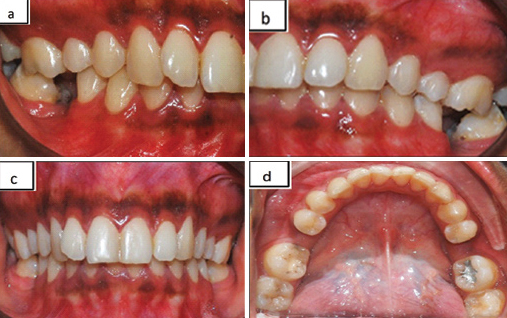

A 19-year-old female patient reported to the department with a mutilated malocclusion [Table/Fig-6a,b] and deep bite [Table/Fig-6c] on a skeletal Class II jaw base. Intraoral examination revealed missing lower first molars bilaterally which were extracted earlier due to caries and also mild lower anterior crowding [Table/Fig-6d]. In this case, we had planned to upright the lingually tipped second molars bilaterally and to mesialize the second molars to the position of the first molars as the third molars were present and this would avoid the prosthetic replacement of the missing molars.

Pre-treatment shows: a,b) mutilated malocclusion; c) deep bite; d) lingually tipped mandibular second molars bilaterally and missing first molars.